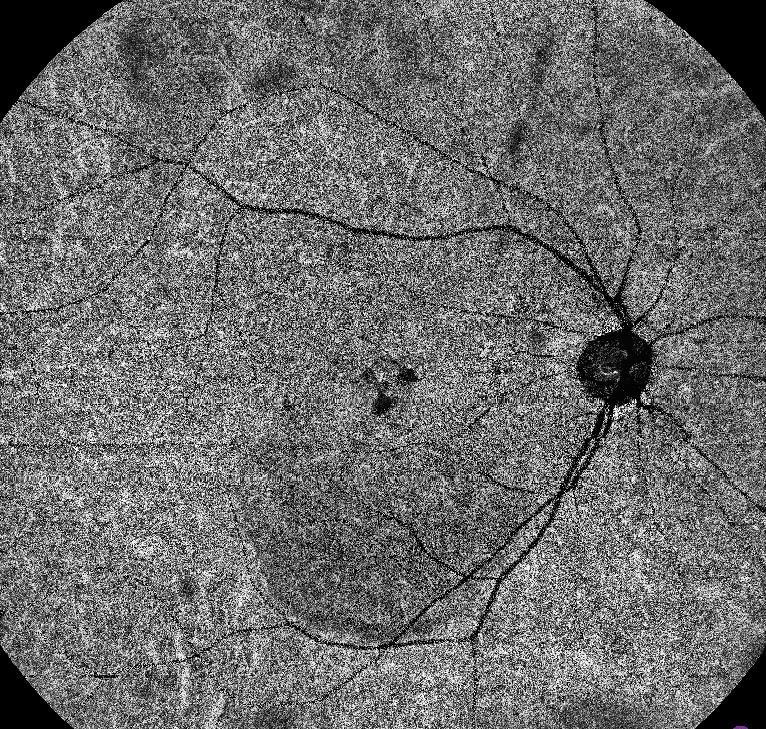

Fundus autofluorescence (FAF) imaging of the right eye demonstrates a large area of diffuse hyperautofluorescence extending from the fovea towards the inferior retina, consistent with the gravitational tract of chronic subretinal fluid. Patchy hypoautofluorescent spots within the area correspond to retinal pigment epithelium (RPE) atrophy. Multiple punctate hyperautofluorescent foci are scattered within and around the detachment zone, likely reflecting areas of photoreceptor and RPE stress. The optic disc shows normal autofluorescence.